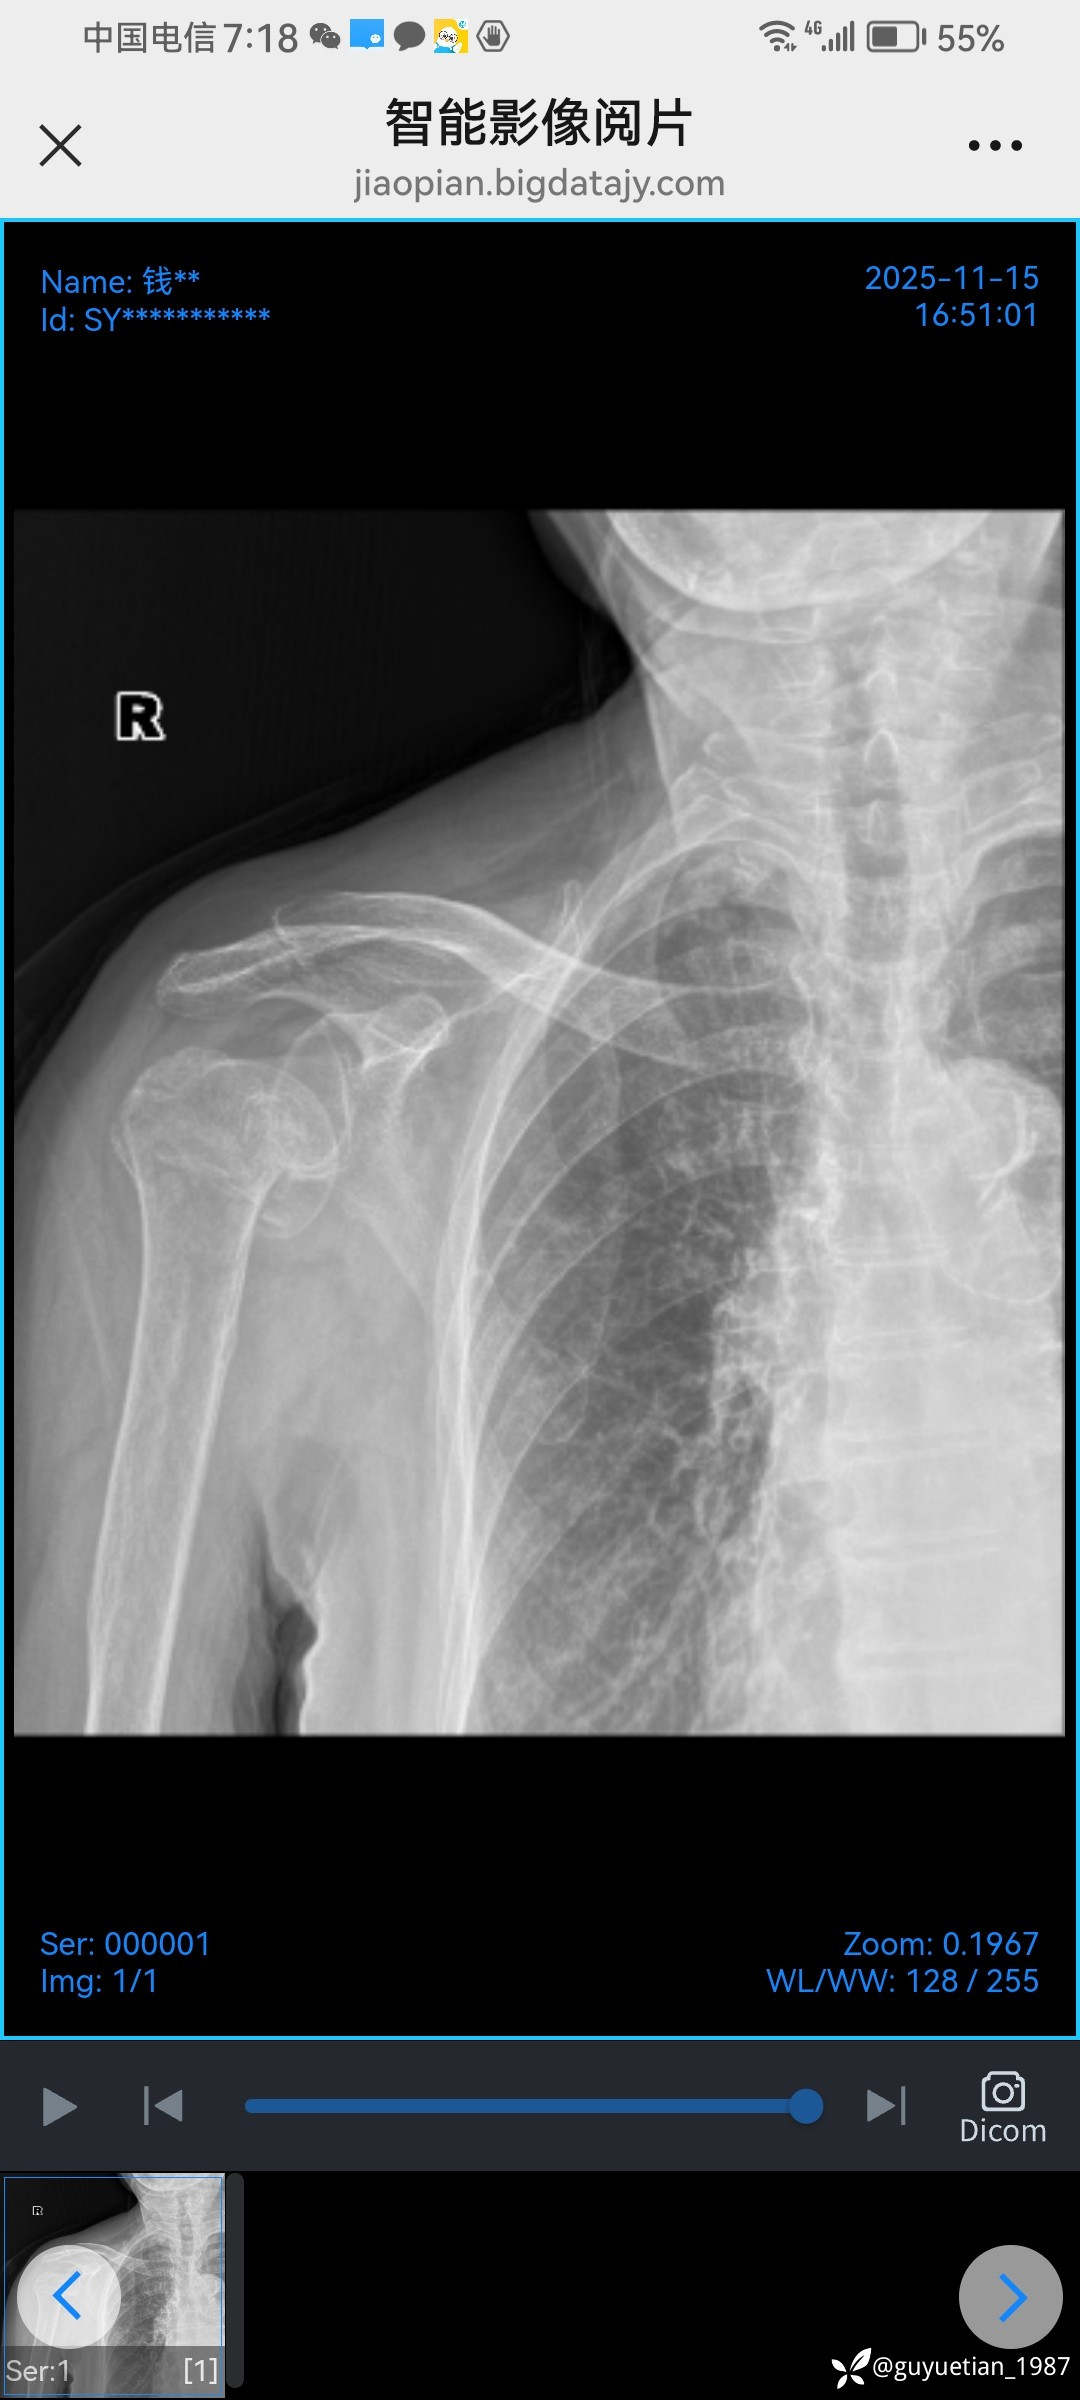

内收型,向前成角